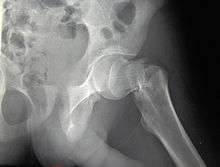

X-ray of the hip joint.

Functional Anatomy

The hip joint, an enarthrodial joint, can be described as a ball and socket joint. The femur connects at the acetabulum of the pelvis and projects laterally before angling medially and inferiorly to form the knee. Although this joint has three degrees of freedom, it is still stable due to the interaction of ligaments and cartilage. The labrum lines the circumference of the acetabulum to provide stability and shock absorption. Articular cartilage covers the concave area of acetabulum, providing more stability and shock absorption. Surrounding the entire joint itself is a capsule secured by the tendon of the psoas muscle and three ligaments. The iliofemoral, or Y, ligament is located anteriorly and serves to prevent hip hyperextension. The pubofemoral ligament is located anteriorly just underneath the iliofemoral ligament and serves primarily to resist abduction, extension, and some external rotation. Finally the ischiofemoral ligament on the posterior side of the capsule resists extension, adduction, and internal rotation. When considering the biomechanics of hip fractures, it is important to examine the mechanical loads the hip experiences during low energy falls.